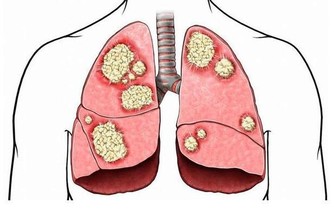

肝硬化:戒菸忌酒勤運動

肝臟是人體最大的代謝器官,我們吃進去的食物都需要肝臟進行合成、分解。在我國,每12個人中就有1人患肝病。

1、忌酒:酒精主要在肝臟被代謝,長期酗酒會傷害肝臟,脂肪肝最早出現,接下來會發展成肝纖維化、酒精性肝病,甚至轉變為肝硬化、肝癌。

2、控制肉食:多吃能增強肝臟解毒功能的食物,如花菜、西紅柿、黃瓜、苦瓜、胡蘿蔔等。

3、壞情緒會傷肝:發火傷肝,心情壓抑、鬱悶也會引起肝氣鬱結。城市生活節奏快、工作壓力大,很多人又缺少運動,找不到宣洩渠道,很容易受不良情緒影響,損害肝臟。

4、按時休息:躺下休息時,進入肝臟的血流量比站立時多數倍,有利於增強肝細胞功能,提高解毒能力。中醫認為,凌晨1-3點是肝經的“值班”時間,此時是養肝最佳時期。

5、勤運動:每天30分鐘的鍛煉,就能避免脂肪過度堆積,預防脂肪肝。